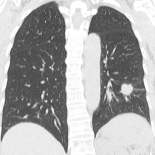

3テスラのMRIなど大学病院クラスの設備と各分野の専門医師が様々な疾患を見逃さない体制

3テスラのMRIなど大学病院クラスの設備と各分野の専門医師が様々な疾患を見逃さない体制

日本人の死亡原因は1位がん 2位心疾患 3位脳疾患です。そして多くの疾患は早期発見、早期治療が何よりも大切です。『林脳神経外科メディカルクリニック』では、大学病院クラスの高性能な医療設備を導入すると共に、各分野の専門医師を集結させ、様々な疾患の早期発見、早期治療を目指しています。

胸部CT 胸部CT

|

|

検査画像のダブルチェック

画像検査の見落としがないよう各科専門の医師による確認後、読影専門医による画像確認のダブルチェックを実施しております。